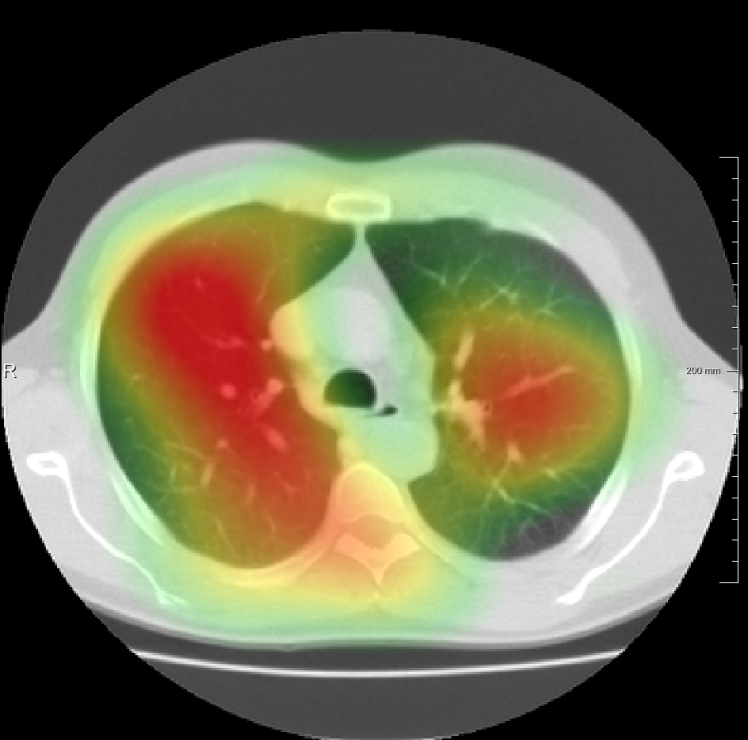

In total we generate 14 basis types of artificial DVFs: 5 single frequency, 4 mixed frequency, 4 respiratory motion and 1 identity. The precise settings of the parameters are available in Table I and examples are given in Fig. 4. The histograms of the Jacobians are also available in this figure. When the spatial frequency is increased, the Jacobian histograms will spread more, which shows that local relative volume changes are increased. The value of , the maximum artificial displacement along each axis, is chosen as 20, 15 and 7 for RegNet4, RegNet2 and RegNet1, respectively.